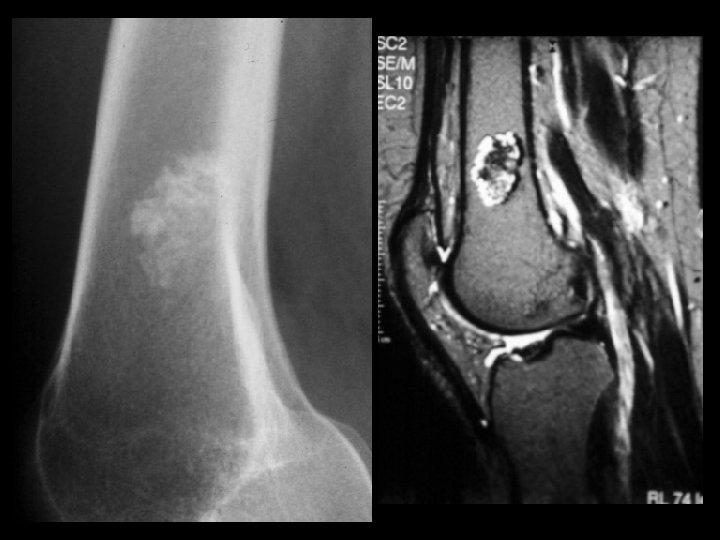

Hemangioma • Findings: – expansile lesion of the proximal tibia containing fine bony septations and a large course calcification – CT scan shows a lacey appearance • ddx: – Paget’s dz – ABC